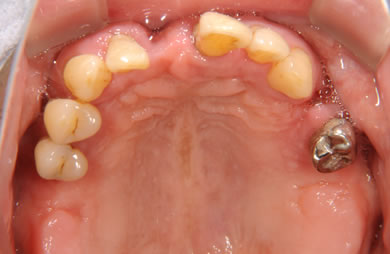

骨再生スピードインプラント治療+AGC連結セラミック治療+セラミック治療

| 治療方針 | ソケットリフト法により上顎洞底部を拳上することにより、骨の無い部分に骨をつくってあげ、インプラント治療を可能にする。さらに歯周病により組織の破壊が著しいので、AGC連結セラミック治療により上顎の審美的回復を行う。 | ||||||||||||||||||||||||||||||||

| 治療内容 | インプラント7本(抜歯AGC即日スピードインプラント+ソケットリフト)、AGCハイブリッドセラミック連結ブリッジ1装置(上顎)ハイブリッドセラミック8本 | ||||||||||||||||||||||||||||||||